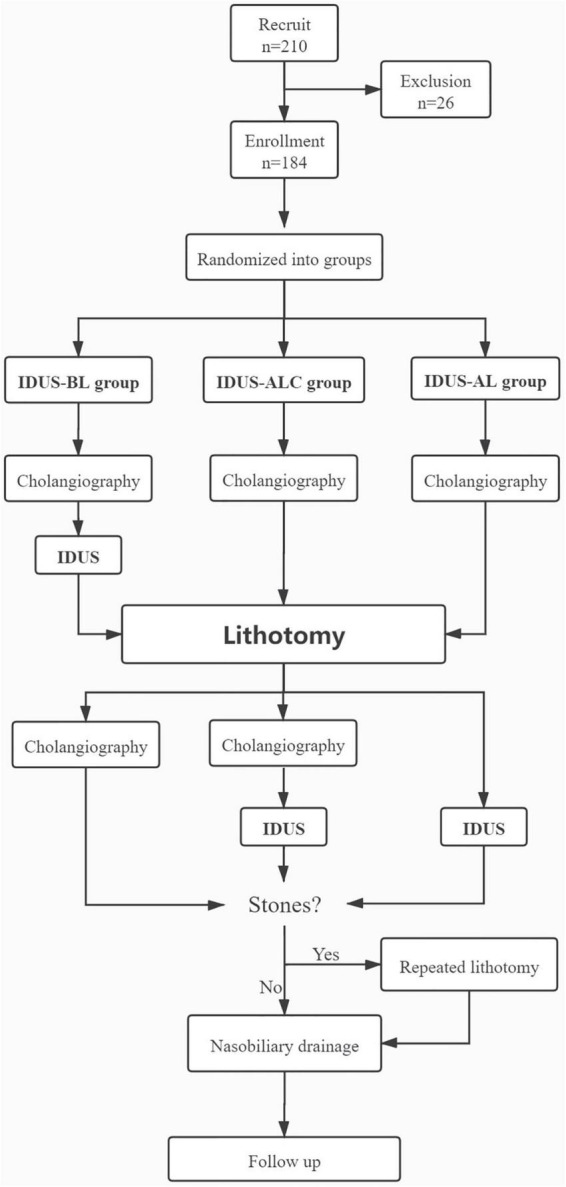

From 2017 to 2020, patients with choledocholithiasis were randomized into IDUS-BL (IDUS performed before lithotomy) group, IDUS-ALC (cholangiography and IDUS performed after lithotomy) group, and IDUS-AL group (IDUS performed after lithotomy) group. The influence of IDUS on the accuracy of prejudgment, the incidence of residual stones, the need for repeated lithotomy (RL), and fluoroscopy time were analyzed.

All patients were prospectively randomized into three groups by generated random numbers: IDUS-BL group (IDUS performed before lithotomy), IDUS-ALC group (cholangiography and IDUS performed after lithotomy), and IDUS-AL group (IDUS performed after lithotomy). Patients in different groups underwent different stone extraction procedural. After successful cannulation, cholangiography was performed in all three groups of patients. Then, the IDUS-BL group underwent IDUS before lithotomy. Next, lithotomies were performed in all groups. After extraction of stones, patients in the IDUS-BL group underwent cholangiography; the IDUS-ALC group underwent cholangiography and IDUS, while the IDUS-AL group only underwent IDUS. If the operator considered incomplete clearance of CBD either by cholangiography or by IDUS, repeated lithotomy (RL) was carried out. The summary flow process is shown in Figure 1. Total clearance rate and fluoroscopy time were carefully investigated according to the following methods.